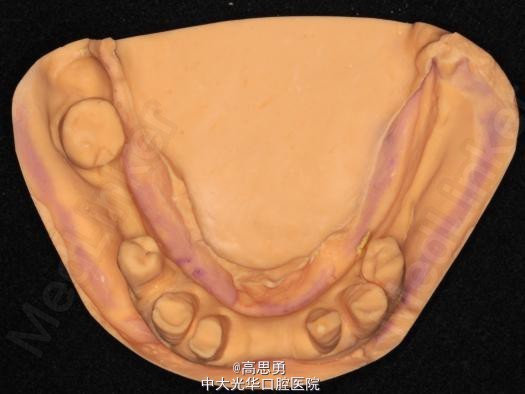

诊断: 1、牙列缺损(上颌肯氏II类I分类,下颌肯氏II类II分类) 2、#13慢性根尖周炎 3、#11、#12、#13、#21、#22、#23、#33、#42、#43、#44楔状缺损 4、慢性牙周炎 治疗计划 1、#13转牙体牙髓科做RCT 2、转牙体牙髓科对#11、#12、#13、#21、#22、#23、#33、#42、#43、#44楔状缺损 充填治疗 3、转牙周科进行牙周洁治 4、择期RPD修复 备选修复方案: 1、#13RCT后截冠后,上下颌覆盖义齿修复; 2、#13RCT后冠修复,上下颌可摘局部义齿修复; 3、#13RCT后树脂充填,上下颌可摘局部义齿修复; 4、#13拔除后,上下颌可摘局部义齿修复。 患者意愿:患者希望尽量保持#13的天然形态,要求费用尽量低,但能恢复正常咀嚼功能。 最终治疗方案:根据患者的年龄、身体状况、治疗周期、经济状况,患者最终选择方案5,即#13RCT后树脂充填,上颌结合卡环式可摘局部义齿修复;下颌可摘铸造支架式局部义齿修复。 治疗过程: 1、临床检查和#13树脂充填 对患者进行全面的口腔检查,用Z350树脂充填#13,调HE,抛光。 2、研究模型 调拌藻酸盐印模材料于2号成品托盘上取上下颌研究模,灌注石膏模型,研究分析、制定治疗计划,并制作个别托盘。 3、基牙预备 对#13近中、#23远中、#27近中、#34近中、#47近中常规制备支托凹,抛光。 4、工作模型 调拌藻酸盐印模材料于个别托盘上。做一定的边缘整塑,取上下颌研究模,灌注石膏模型。 5、试戴支架 检查支架的就位、固位可,无翘动,调HE,抛光,用蜡堤取颌位关系,上颌架,排牙,比色C4。 6、试排牙 检查义齿的就位、固位可,无翘动,观察人工牙的咬合状况,尖窝接触良好,正中颌位能重复,患者无诉不适,面容自然,外观满意。送加工厂充胶制作最终修复体。 7、试戴 检查义齿的就位、固位可,无翘动,咬合关系正确,利用咬合纸检查,上下颌尖窝接触均匀全面,抛光,患者表示满意,嘱注意事项,定期复诊。